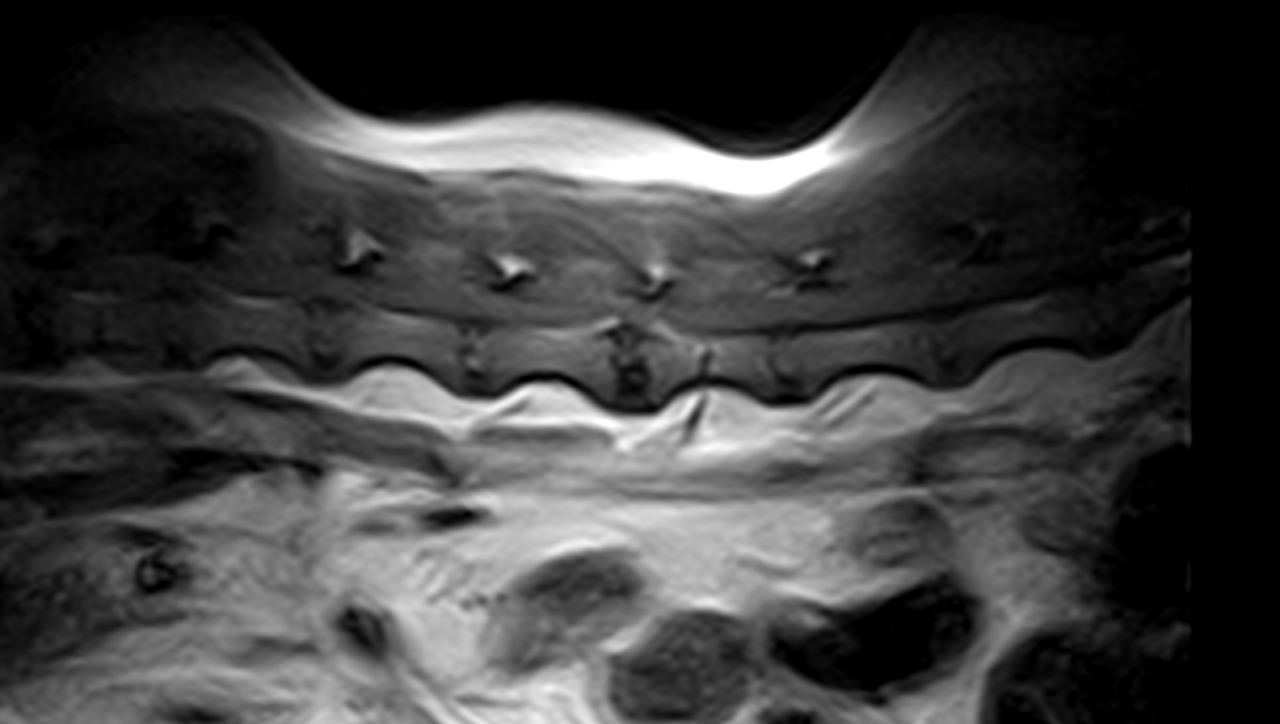

中年齢のミニチュア・ダックスさんがG1の椎間板ヘルニアを内科的に管理していたが、急に症状が悪化、腰の痛みと起立出来なくなったとの事で来院されました。幸いにも深部痛覚は保たれていました。Laminectomyで脊柱管内に侵入すると静脈洞から顕著に出血が確認されました。椎間板物質の摘除と共に脊髄の除圧を行いました。5日後には随意運動が回復し、7日で退院となりました。内科的な管理を行う場合は厳格なケージレストが行えないと、一気に神経症状が悪化することがあります。